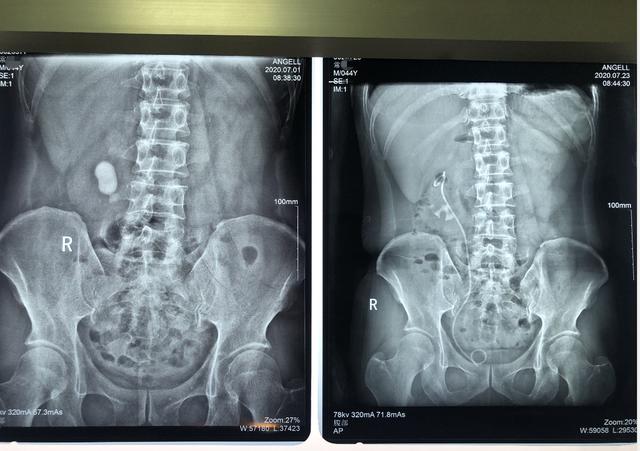

患者术前术后对比图,效果非常好

通过消炎对症治疗后,王怀亮为患者常先生施行了Ⅰ期右纤维肾镜无创保肾取石术。术中因结石过大,为避免结石堵塞输尿管造成梗阻损坏肾脏,王怀亮决定分批次碎石,手术顺利击碎大部分结石。7月22日,常先生接受了Ⅱ期右纤维肾镜无创保肾取石术。

王怀亮说:第1次大部分结石都打碎了让它排出来,第2次就把碎石头取出来了,术后患者恢复的很好。

结石阴霾散尽,又保住了肾脏,常先生对这个结果非常满意,感激之情溢于言表。他紧紧拉住王怀亮的手,一个劲地感谢。目前,常先生已于7月23日恢复出院。